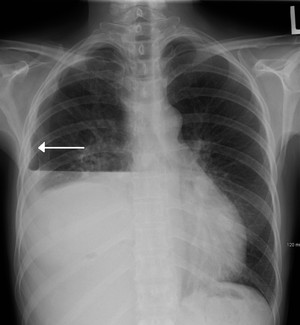

Hydropneumothorax

| A hydropneumothorax with white arrow point to the lung's pleura | |

Hydropneumothorax is defined as the presence of both air and fluid within the pleural space surrounding the lung. An upright chest x-ray will show air fluid levels. The horizontal fluid level is usually well defined and extends across the whole length of hemithorax.